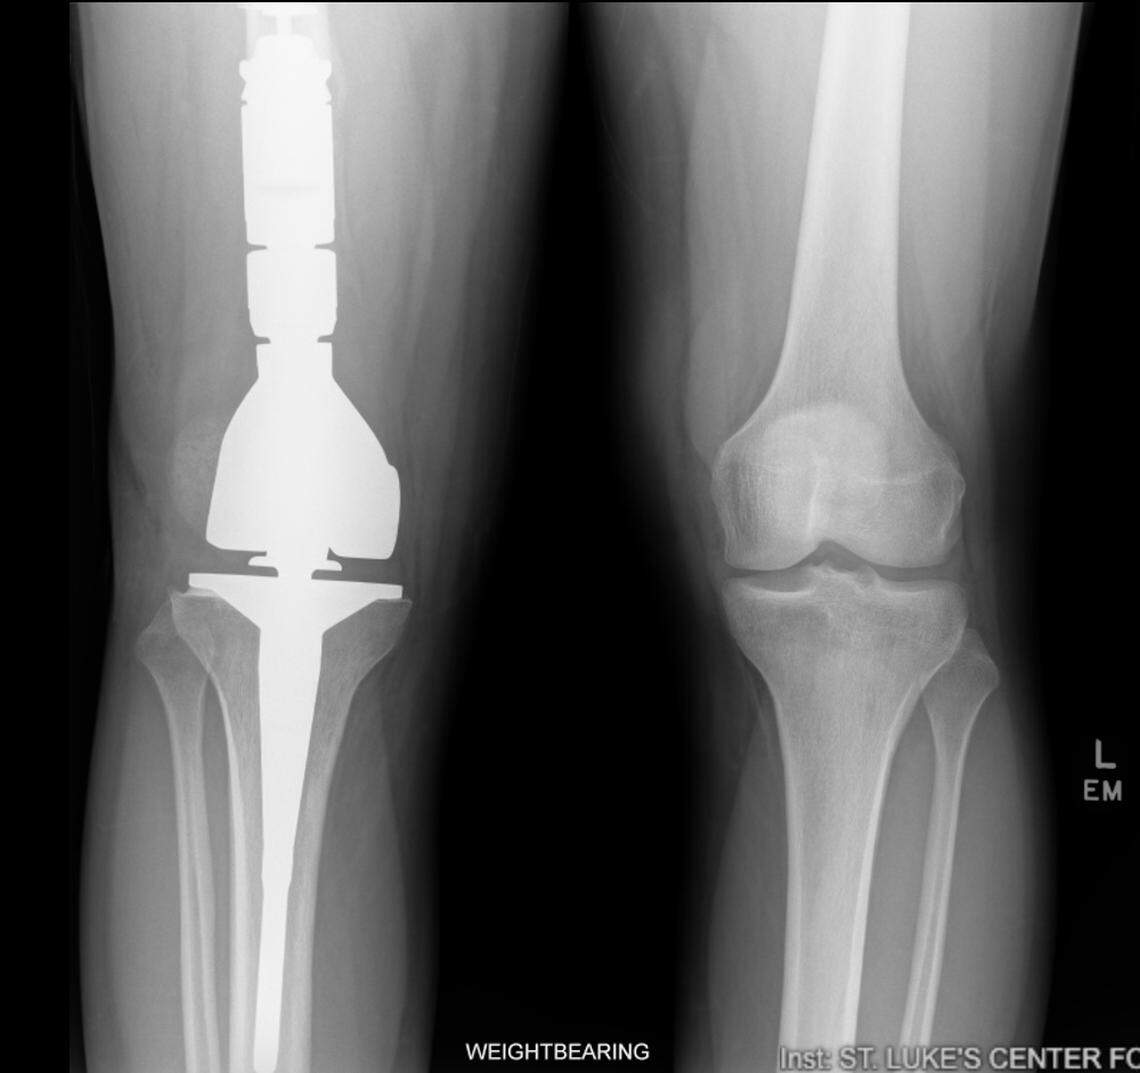

Aggressive treatment followed his aggressive version of cancer. He began 10 weeks of chemotherapy before surgeons in Salt Lake City replaced his entire right knee on Jan. 9, 2025. The nine-hour operation left his lower leg intact. But the compress implant required removing the lower third of his femur and boring into his tibia to keep the new prosthetic knee in place.

Parker lost every ligament in the process, keeping only his original kneecap. The rest is all metal.

An x-ray shows Eli Parker’s knee implant three months after surgery.

An x-ray shows Eli Parker’s knee implant three months after surgery. Courtesy of Alison Parker